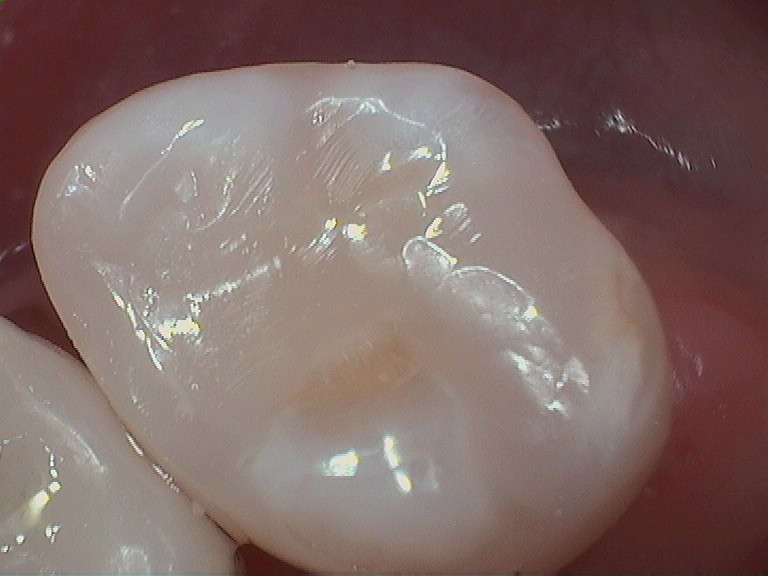

Gallery